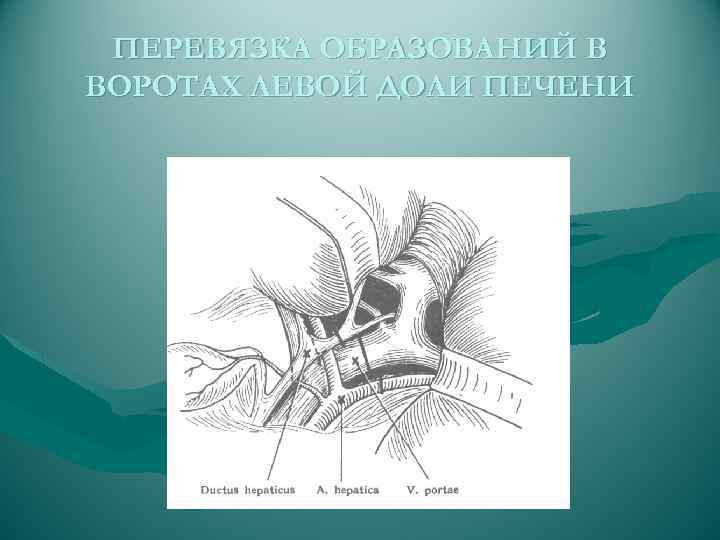

ПЕРЕВЯЗКА ОБРАЗОВАНИЙ В ВОРОТАХ ЛЕВОЙ ДОЛИ ПЕЧЕНИ

ПЕРЕВЯЗКА ОБРАЗОВАНИЙ В ВОРОТАХ ЛЕВОЙ ДОЛИ ПЕЧЕНИ